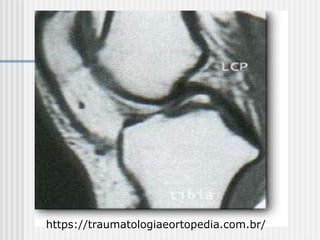

Ressonância magnética

 Fase aguda:

Precisão 96% a 100%.

 Fase crônica: Precisão 23%.